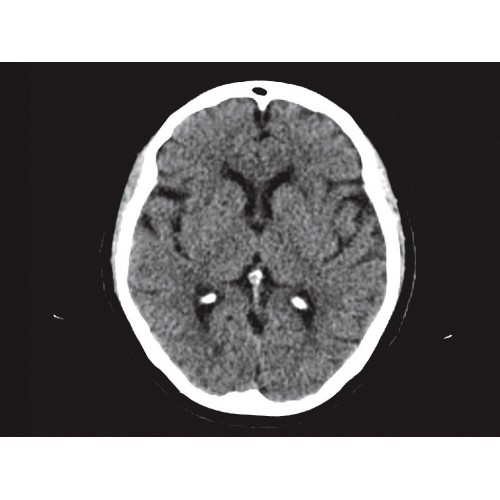

Позволяет проводить комплексные исследования всех анатомических зон, включая нейровизуализацию, ангиографию, исследования органов грудной и брюшной полости. Особенно эффективен для раннего выявления онкологических заболеваний.

Специализированные исследования